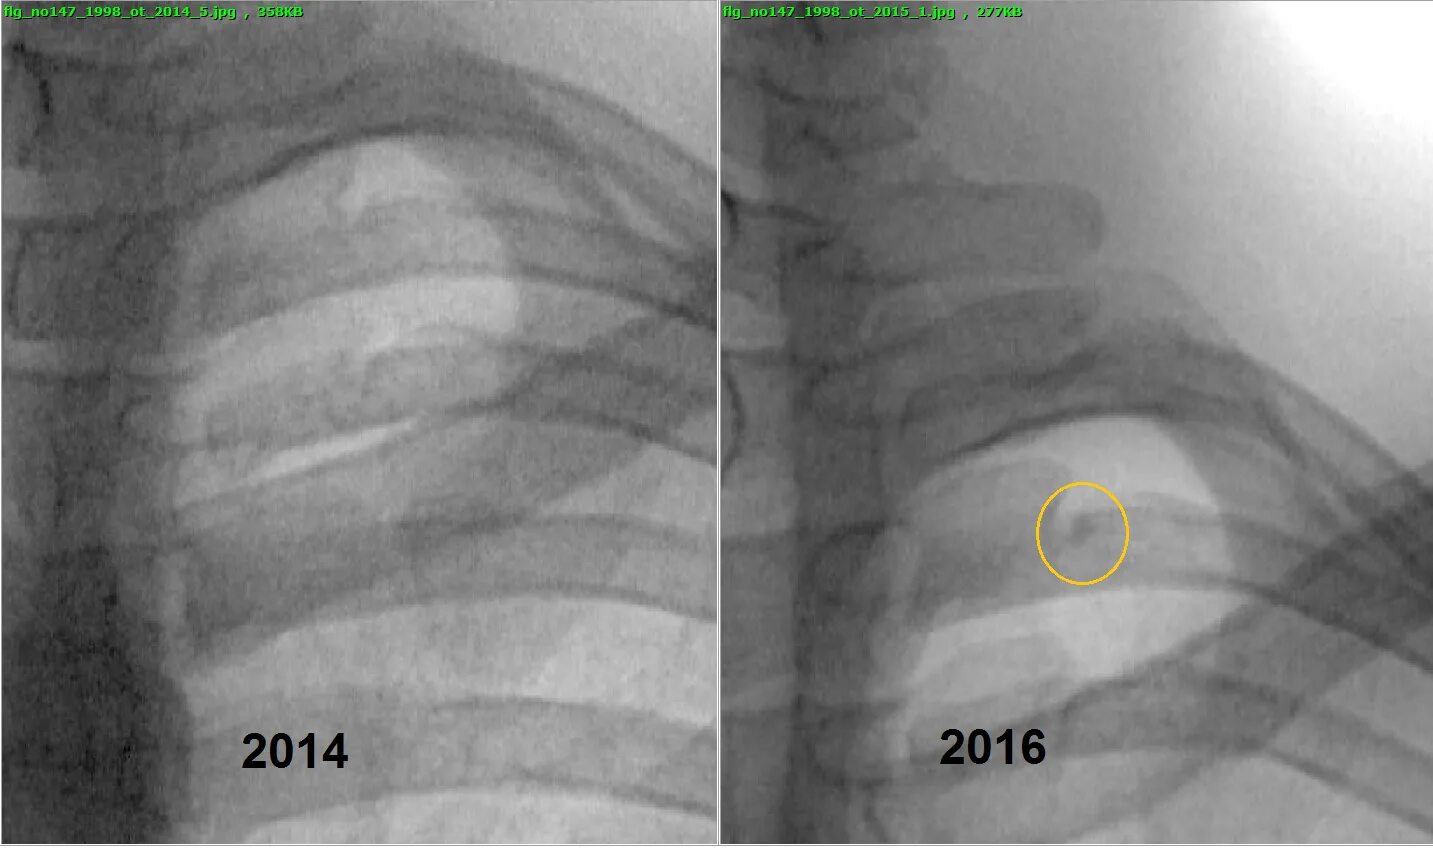

Уплотнение слева